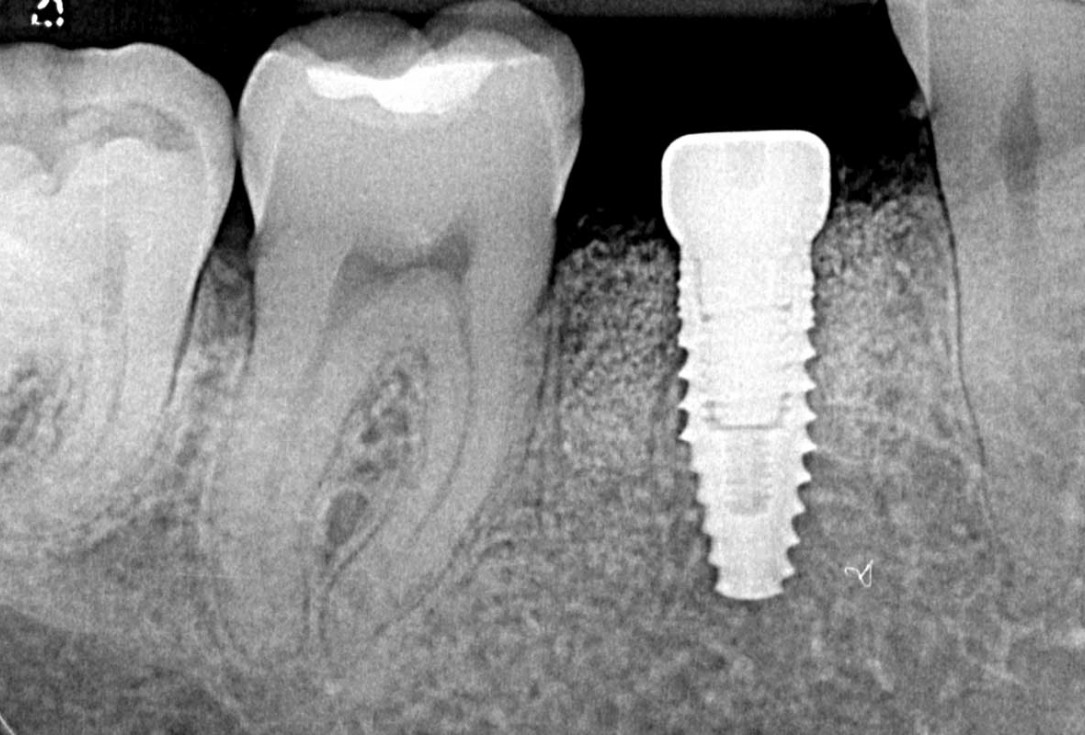

03/25 - Situation after tooth extraction and implant placementImmediate implant placement and peri-implant bone augmentation with cerabone® plus - Dr. R. Block Veras

08/25 - Radiographic control immediately after augmentationImmediate implant placement and peri-implant bone augmentation with cerabone® plus - Dr. R. Block Veras